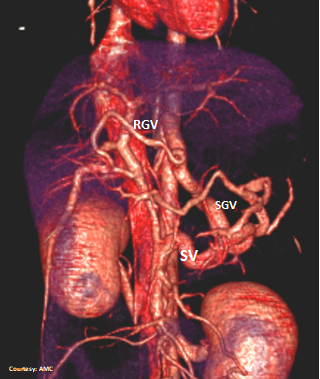

Does the RIGHT GASTRIC VEIN (RGV) contribute blood to the shunt?

Does the SHORT GASTRIC VEIN (SGV) contribute blood to the shunt?